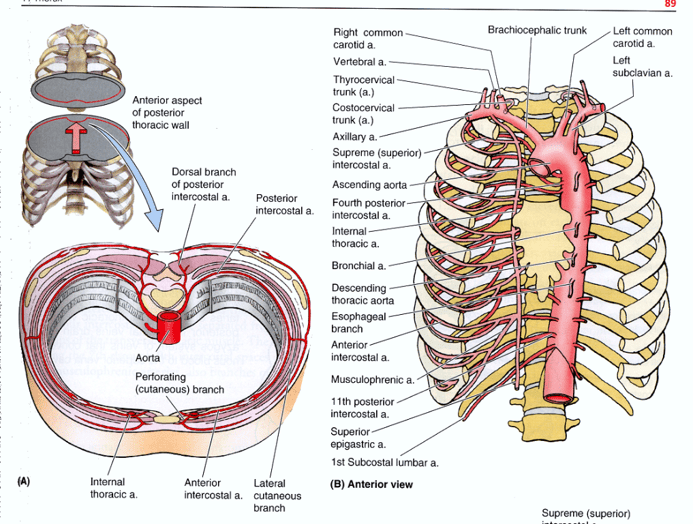

- Blood supply to the rib cage originates from what 2 places?

- what 2 arteries supply the intercostal spaces of the rib cage

- what branch off of the subclavian artery goes down specifically to the diaphragm?

aorta and subclavian artery

Anterior and posterior intercostal arteries

notice how branches from the aorta go around and supply the rib cage

the internal thoracic artery

look at picture

study picture

Identify/describe the intercostal artery pathway?

- Intercostal arteries/veins run in the ___________ aspect of

the intercostal space?

- They are ________ to the “superior rib” of the intercostal space?

- Collateral branches of intercostal arteries/veins run in the _________ aspect of the intercostal space

superior aspect

inferior

inferior

go back and rememeber the subclavian artery and how it had the VA, the thyrocervical trun and the costocervical trunk.....one branch from the costcervical trunk that went up to the skull was the deep cervical artery....what is the branch of this trunk that goes down?

what then branches from the artery?

the supreme intercostal artery

the 1st and 2nd posterior intercostal arteries

notice the subclavian, the costcervical trunk and the deep cervical artery and the supreme intercostal artery...then notice how it splits off into 2 branches under the clavicle

the 3rd through the 11th intercostal arteries branch off from what?

notice it in the picture?

from the aorta

Posterior intercostal arteries:

- There are only 11 “posterior intercostal arteries” that supply what?

- The ________ which arises from aorta helps supply what as it runs inferior to the rib?

the 11 intercostal spaces

subcostal artery

the 12th rib

notice how in the picture you can see the subcostal artery down below the ribs as it branches from the aorta

Anterior intercostal arteries:

- These arteries branch from where?

- then this originates from where?

internal thoracic artery

- Internal thoracic artery originates from subclavian artery

the internal thoracic artery comes from the ____________ vein and then runs behind the anterior ________?

subclavian vein

anterior sternum

notice the internal thoracic artery coming down right near the sternum

The Anterior intercostal arteries supply which intercostal spaces?

- The lower intercostal spaces supplied by what?

1-9

posterior intercostal arteries

notice how the intercostal arteries run superior and inferior in the intercostal spaces

look at all the arteries and their relationship

look at how the posterior intercostal arteries come from the back and wrap around the intercostal spaces from the back

look at picture